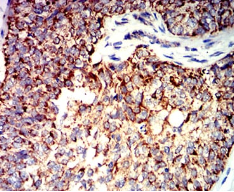

BAK1 Mouse Monoclonal antibody[2H9H7]

IHC    1/200 - 1/1000